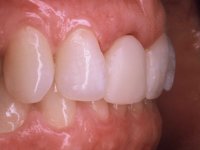

After the impression of the implant using a double-mix technique with double viscosity and the collection of shape and color information by the ceramist, we proceed with the work. In the model, a syn octa was placed over the implant, and a screw was placed on it to assess its emergence in relation to the incisal edge. Then, an adequate emergence profile in the artificial gingiva was prepared. A abutment with characteristics suitable for overbite and simultaneously capable of receiving a veneer was waxed on top of this scenario. This waxing gave rise to the manual milling of a very personalized abutment. An infrastructure in Zr was also made for the veneer with a very great adaptation to the abutment. On this infrastructure ceramics were placed. Ceramic fluorescence sought to compensate for the lack of fluorescence that Zr had and obviously further customize the aesthetics. The adhesive bridge was removed and the definitive work was placed. The syn octa was initially tightened with 35 N to the implant and then the Zr abutment was tightened over the syn octa with 15 N. The access hole was plugged and then the veneer was cemented with resin-reinforced glass ionomer. After 15 years, the patient returned to the consultation with tooth mobility. Fortunately, nowadays we have the possibility of having dynamic tightening wrenches that allow tightening screws with greater inclinations. An access cavity was made without damaging the incisal edge of the veneer. Tightening was done with a dynamic wrench with 15 N torque. The hole was covered with Teflon and filled with composite resin. This solution allowed the problem to be solved in a simple and economical way.